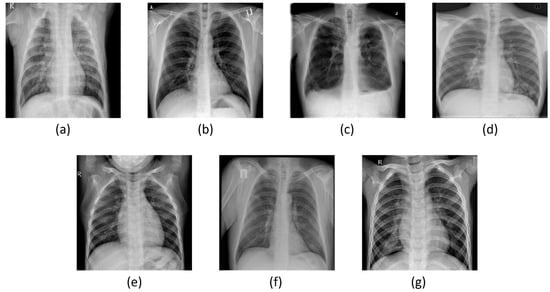

- To create a comprehensive dataset encompassing seven distinct classes (COVID-19, normal, viral pneumonia, bacterial pneumonia, fibrosis, lung opacity, and tuberculosis), four publicly available datasets were combined.